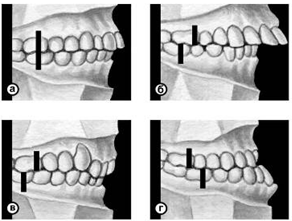

Кроме аномалий П. в сагиттальной плоскости существуют аномалии П. в вертикальной и трансверзальной плоскостях. К основным вертикальным аномалиям (определяются по отношению к горизонтальной плоскости) относится открытый и глубокий П. Открытый П. (рис. 7, а) — наличие щели между зубными рядами при их смыкании, чаще в области передних зубов, реже в области боковых. Иногда смыкаются только последние моляры, что приводит к выраженным нарушениям жевательной функции и особенно речи. При глубоком П. (рис. 7, б) передние зубы одной из челюстей в значительной степени перекрывают коронки зубов-антагонистов, нижние резцы не опираются на зубные бугорки верхних резцов, а соскальзывают к их десневому краю, что приводит к постоянному травмированию десен и неба; нижняя часть лица укорочена за счет уменьшения или дистального положения подбородка.

К трансверзальным аномалиям, определяемым по отношению к сагиттальной плоскости, относится перекрестный П. (рис. 7, в), при котором верхний зубной ряд в области боковых участков в значительной степени перекрывает нижний зубной ряд (латерогнатический П.) или нижний перекрывает верхний (латерогенический П.).

Рис. 7а). Схематическое изображение челюстей при открытом прикусе.

Рис. 7б). Схематическое изображение челюстей при глубоком прикусе.

Рис. 7в). Схематическое изображение челюстей при перекрестном прикусе.